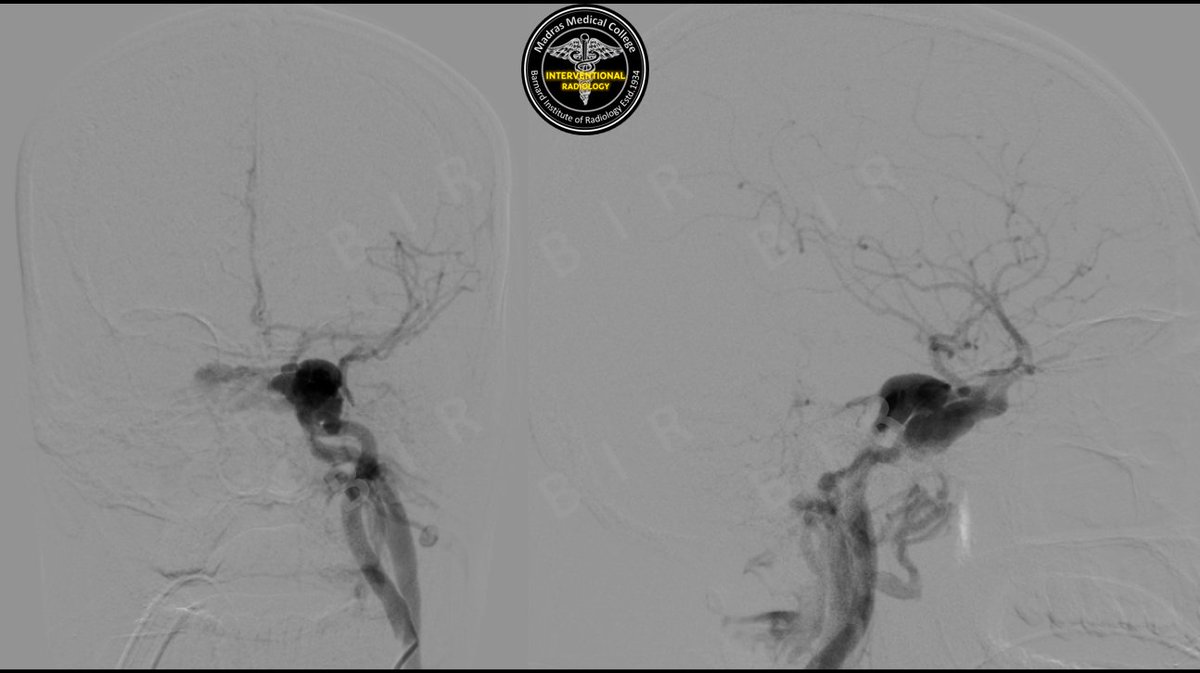

Ca retromandibular trigone>Massive per oral bleed>IMA blowout>#justglueit #irad #MedTwitter @ISVIRIndia @cirsesociety @SIRspecialists @karananandpara @PulkitRangarh @Murthy_CS_ @ChengaziMD @DrAjityadav @keithppereira